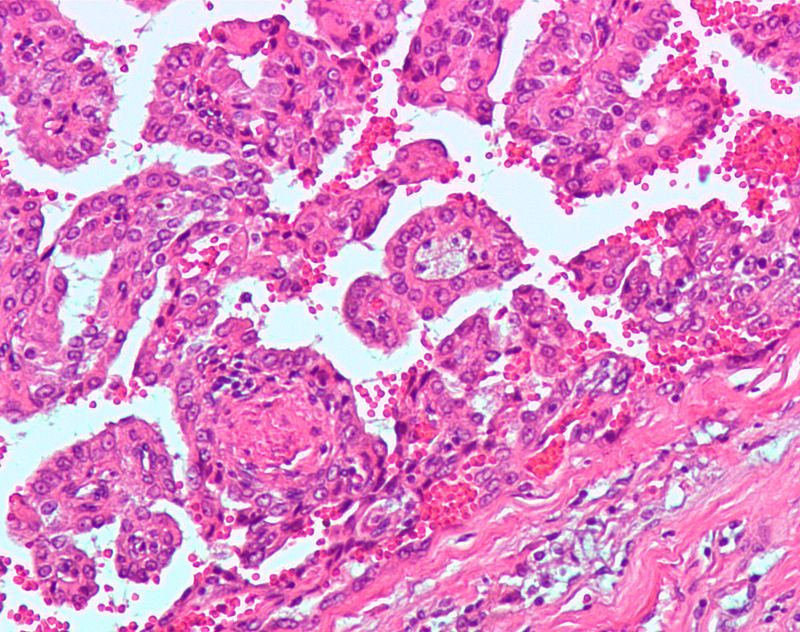

Renal Cell Carcinoma (RCC)

Renal cell carcinoma (RCC) is a malignant cancer cells are located in the lining of kidney tubules, which are incredibly tiny tubes. This condition is known as renal cell carcinoma.

When examined under a microscope, the most common variant of renal cell carcinoma shows clear cytoplasm or a clear cell type.